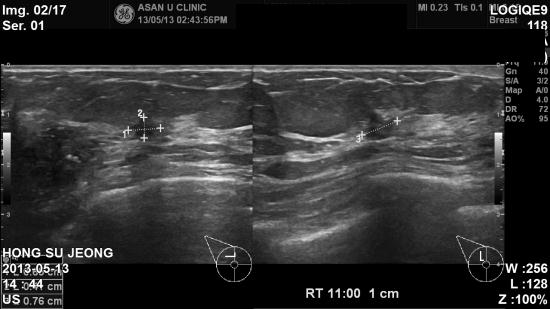

샤워하다 오른쪽 유방에 멍우리 및 통증있어 내원하신 54세 여성분이십니다.

촉진시 우측 유방 및 임파절 만져지는 혹있었으며,

본원 초음파상 우측 유방 9 : 30, 11시 방향 혹 과, 우측 임파절 비대소견으로

조직검사 및 세침검사 시행하여,

조직검사 결과 상 우측 침윤성 유관암 및 겨드랑이 전이로 진단 되었습니다.